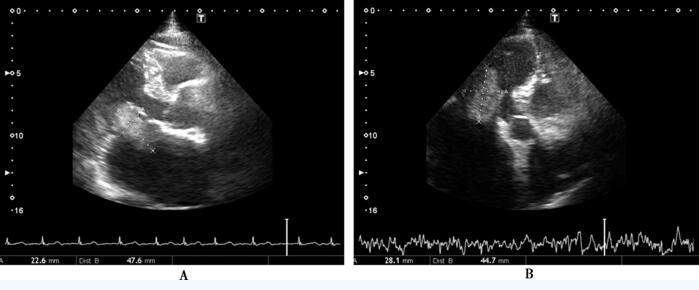

进一步行超声心动图:双心房内径大,以左心房为著,其内见异常占位性病变,大小约48mm×23mm,随心动周期舒张期脱入二尖瓣口,收缩期回到左心房,考虑血栓可能、左心房黏液瘤不除外;双心室不大,室间隔室壁厚度正常,收缩幅度正常低限;主动脉瓣增厚、回声增强、开放不受限,余瓣形态未见异常;心包腔内未探及液性暗区,升主动脉内径宽;多普勒探及少~中量二尖瓣反流,少量三尖瓣、主动脉瓣反流(图75-1)。

图75-1 入院超声心动图

A:胸骨旁长轴切面示左心房占位团块,48mm×23mm,舒张期飘向左心室方向,收缩期回到左心房; B:心尖长轴切面示左心房占位团块,45mm×28mm,舒张期飘向左心室方向,收缩期回到左心房